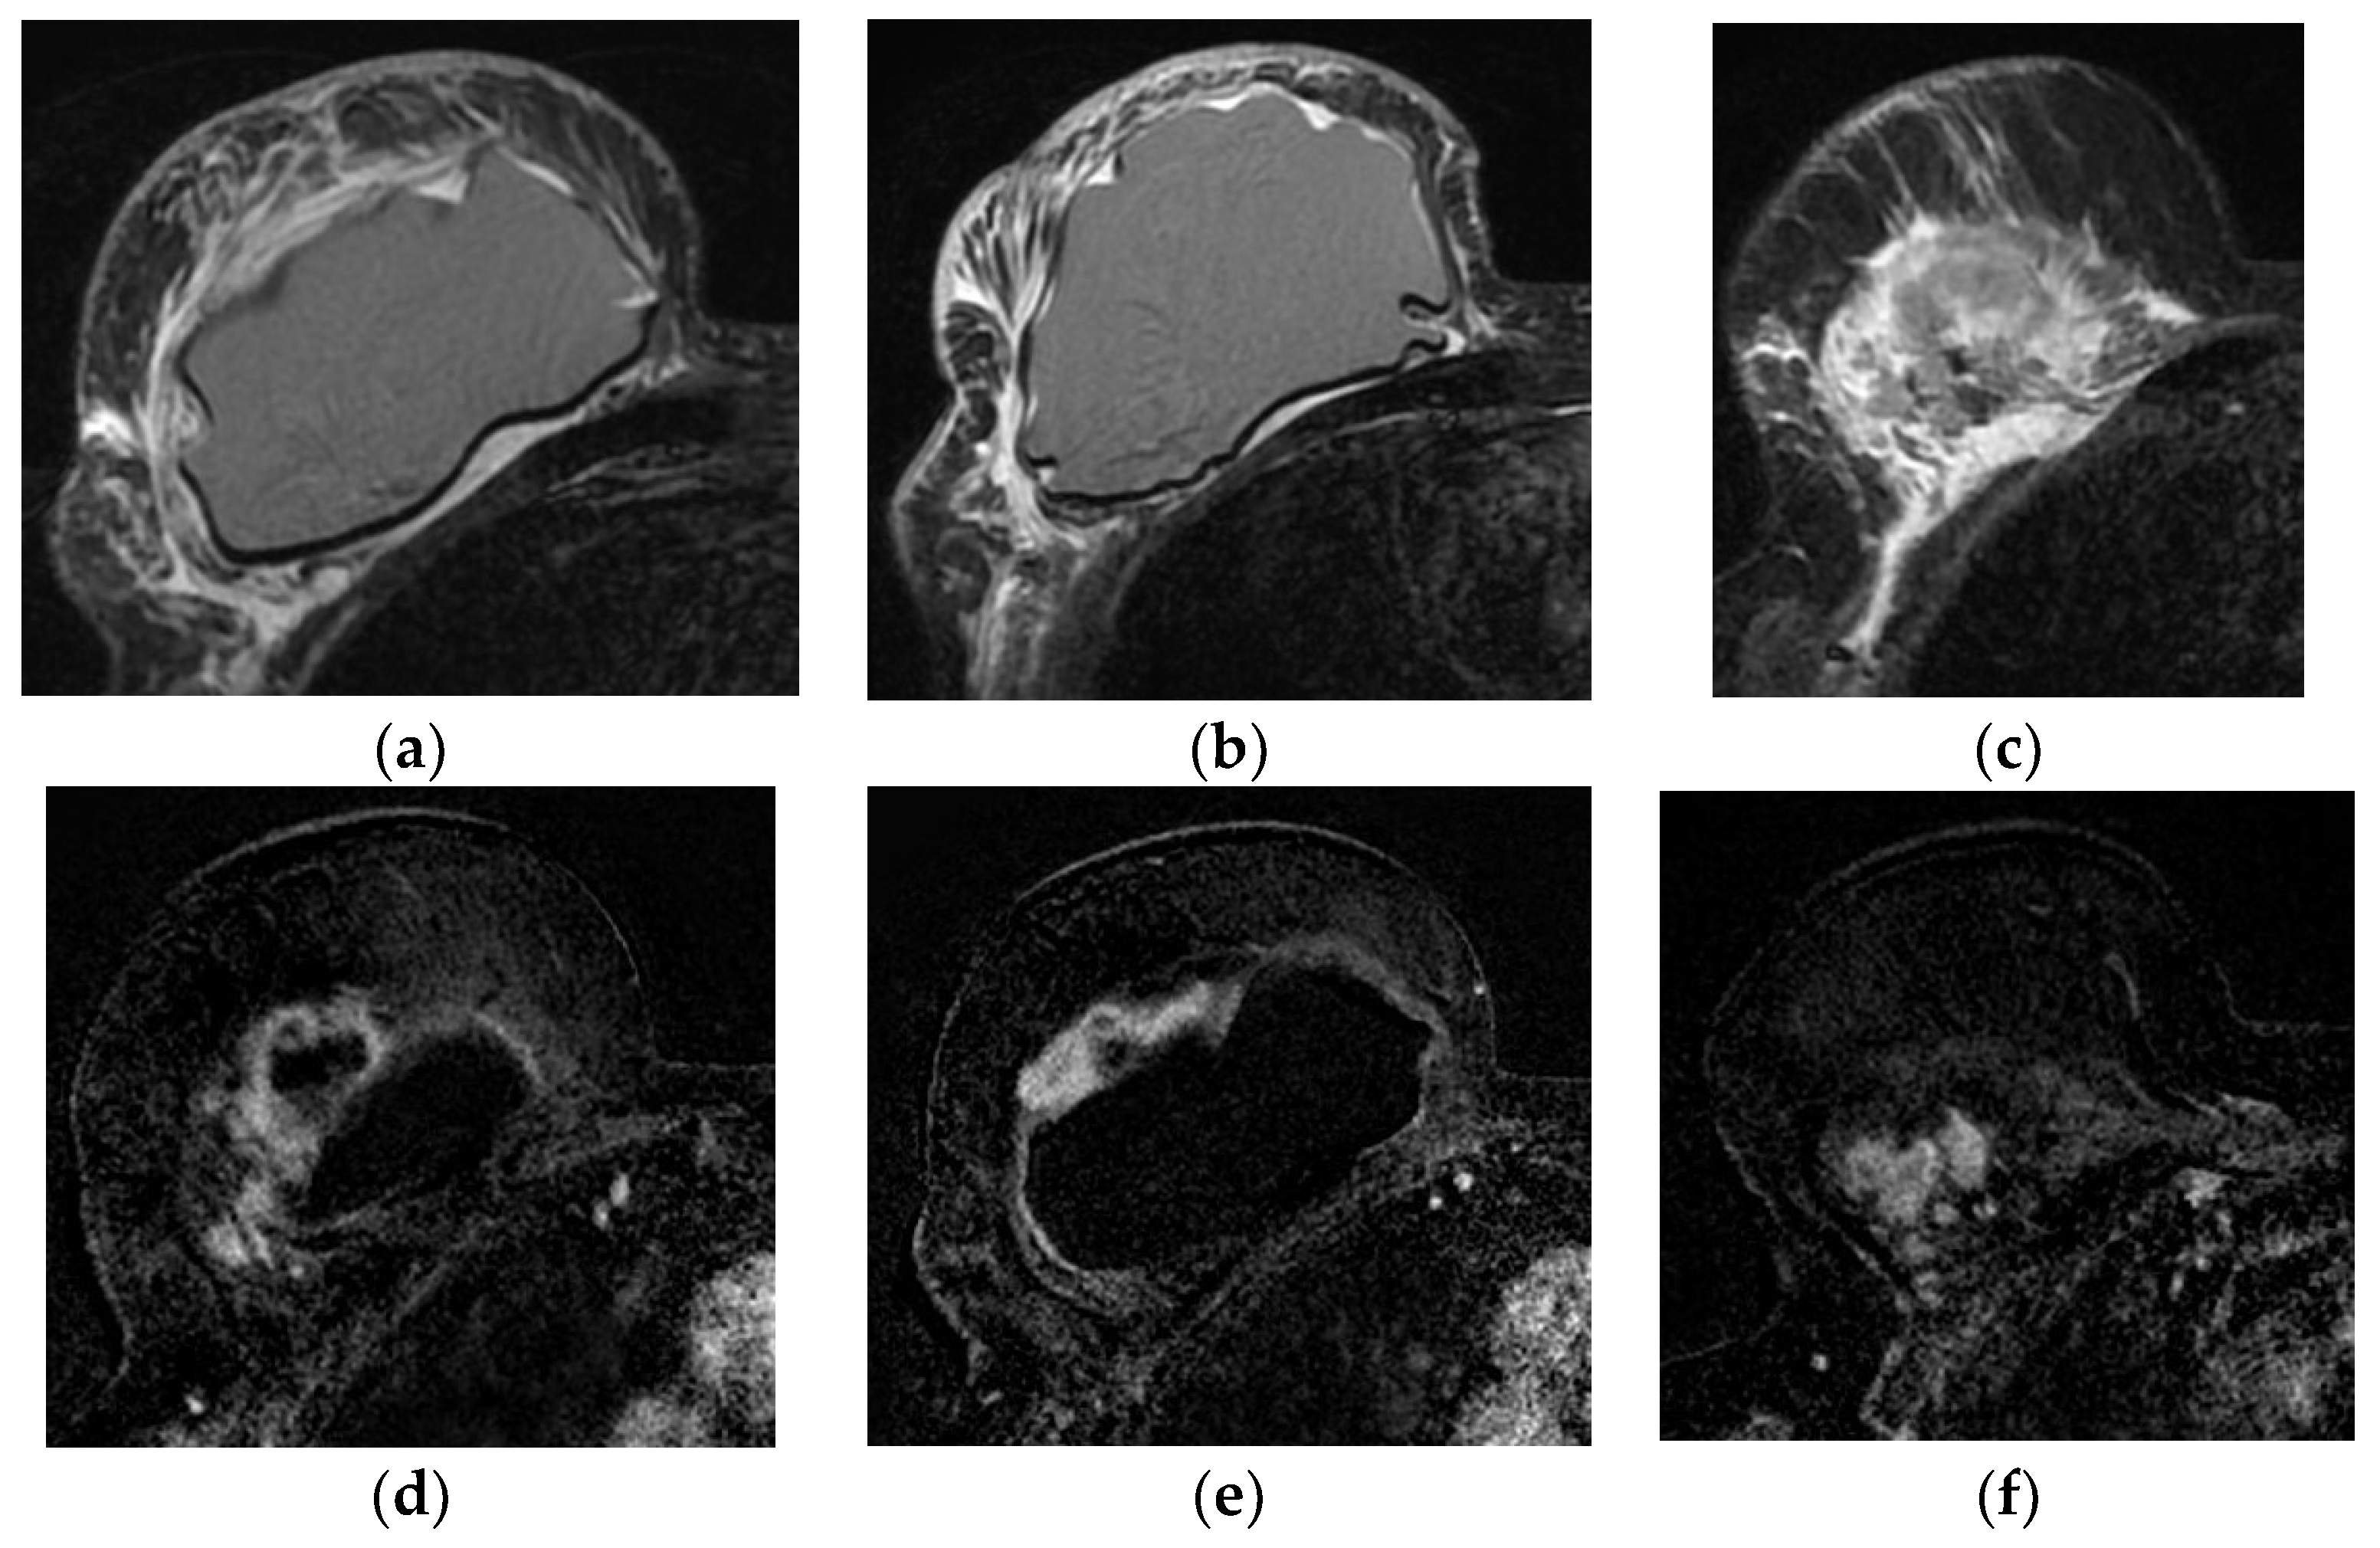

5.1.3. Fat Necrosis

- Kerridge, W.D.; Kryvenko, O.N.; Thompson, A.; Shah, B.A. Fat Necrosis of the Breast: A Pictorial Review of the Mammographic, Ultrasound, CT, and MRI Findings with Histopathologic Correlation. Radiol. Res. Pract. 2015, 2015, 613139. [Google Scholar] [CrossRef] [PubMed]

- Taboada, J.L.; Stephens, T.W.; Krishnamurthy, S.; Brandt, K.R.; Whitman, G.J. The many faces of fat necrosis in the breast. Am. J. Roentgenol. 2009, 192, 815–825. [Google Scholar] [CrossRef] [PubMed]

- Daly, C.P.; Jaeger, B.; Sill, D.S. Variable appearances of fat necrosis on breast MRI. Am. J. Roentgenol. 2008, 191, 1374–1380. [Google Scholar] [CrossRef] [PubMed]

- Trimboli, R.M.; Carbonaro, L.A.; Cartia, F.; Di Leo, G.; Sardanelli, F. MRI of fat necrosis of the breast: The “black hole” sign at short tau inversion recovery. Eur. J. Radiol. 2012, 81, e573–e579. [Google Scholar] [CrossRef] [PubMed]